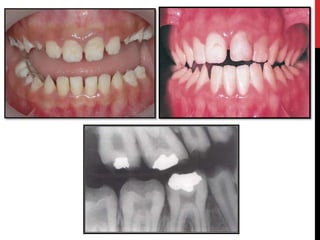

Hypoplastic amelogenesis imperfecta:

Basic alteration centers on inadequate deposition of enamel matrix.

• Generalized pattern

• Localized pattern

• Autosomal dominant smooth pattern

• X- linked smooth pattern

• X-linked rough pattern

Hypoplastic amelogenesis imperfecta: Basicalteration centers on inadequate deposition of enamel matrix. • Generalized pattern • Localized pattern • Autosomal dominant smooth pattern • X- linked smooth pattern • X-linked rough pattern

• #28 Hypoplastic amelogenesis imperfecta: Basic alteration centers on inadequate deposition of enamel matrix. Generalized pattern: Pin point to pin head sized pits are scattered across the surface of the teeth. The buccal surface of the teeth are affected more severely and the pits are arranged in rows or columns. Staining of the pits may occur. The enamel between pits is of normal thickness, hardness and coloration.

• #31 Autosomal dominant smooth pattern: The enamel of all teeth exhibits a smooth surface and is thin hard and glossy. The absence of appropriate enamel thickness results in teeth that are shaped like crown preparations and demonstrate open contact points. The color of teeth varies from opaque white to translucent brown. Radiographically the teeth exhibit a thin peripheral outline of radiopaque enamel.

• #32 X-linked smooth pattern Exhibits diffuse thin, smooth, and shiny enamel in both dentitions. The teeth often have the shape of crown preparations,and the contacts points open. The color varies from brown to yellow-brown. Radiographs show a peripheral outline of radioopaque enamel.unerupted teeth undergo resorption. An open bite is seen in almost all males and in a minority of females. X-linked rough pattern The enamel is thin, hard and rough surfaced.As in smooth forms, the teeth taper towards the incisial occlusal surface and demonstrate open contact points. The color varies from white to yellow white. The enamel is denser than that seen in smooth patterns and the teeth are less vulnerable to attrition. Radiographs exhibit a thin peripheral outline of radio dense enamel.